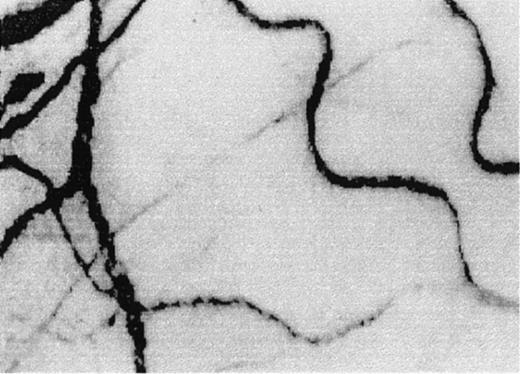

Two frame-captured steady-state images of the conjunctival microcirculation showing additional microvascular abnormalities.

Optical magnification, × 4.5; onscreen magnification, × 125. (A) Inadequate vascularization (avascularity), two types of comma signs (CS1 and CS2), blood sludging (S), and the intermittent boxcar (sluggish) blood flow phenomenon (BC) are present. (B) Another view of comma signs (CS1), blood sludging (S), and the boxcar blood flow phenomenon (BC).